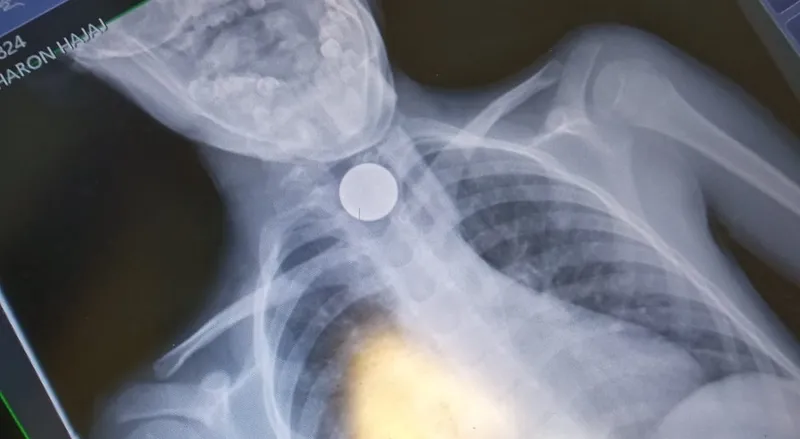

נס בבני ברק: צוותי הרפואה של איחוד הצלה העניקו הערב (שלישי) סיוע ראשוני והצילו את חייו של ילד בן 7 שנחנק ממטבע של 10 אגורות בביתו בבני ברק.

אפי פלדמן ראש סניף איחוד הצלה בבני ברק סיפר: "כשהגעתי למקום נמסר לנו כי הילד נחנק ממטבע של 10 אגורות שנתקע לו בקנה הנשימה. פיניתי אותו באמבולנס איחוד הצלה למרכז הרפואי מעייני הישועה תוך כדי שייצבנו את מצבו".